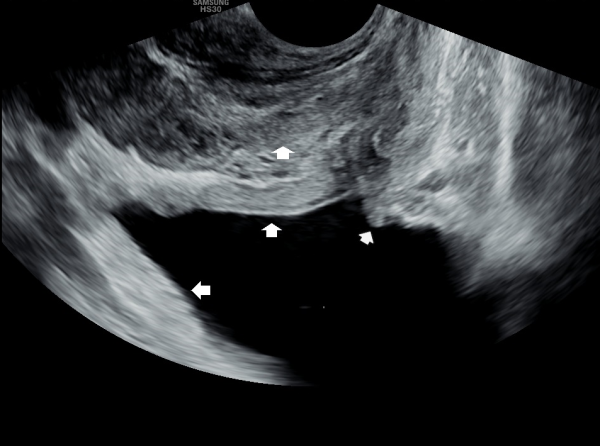

서울가정의학과의원에 첫 내원 당일 지난 5개월동안 회음부 통증과 배뇨장애로 타 비뇨기과 여러곳에서 치료를 했으나 증상의 호전이 없다고 내원 당일 검사한 경직장 전립선 초음파 검사상 사정관 입구의 석회화와 사정관의 섬유화 그리고 정낭의 낭종이 관찰되는 초음파 자료입니다.

On the first visit to Seoul Family Medicine Clinic, the patient reported having perineal pain and urination problems for the past five months, despite receiving treatment at several other urology clinics with no improvement.

A transrectal prostate ultrasound performed on the day of the visit showed calcification at the opening of the ejaculatory duct, fibrosis (scarring) of the duct itself, and cysts in the seminal vesicles.

또한 방광벽이 배뇨장애로 두꺼워져 과민성 방광이 의심되는 초음파 사진입니다.

The ultrasound image also shows that the bladder wall has become thickened, likely due to urination difficulties. This may suggest an overactive bladder, which can cause frequent or urgent urination.

내원 당일 경직장 전립선 초음파 검사상 오랜 세월동안 사정관의 벽이 수명을 다한 거짓 중층 원주 상피 세포가 탈락되어 사정관 입구에 막혀 두텁게 쌓여 있고 요도에도 탈락된 상피 세포가 쌓여서 정낭과 정관 그리고 전립선액 과 배뇨등의 순환 장애를 보이고 있는 경직장 전립선 초음파 사진입니다.

This transrectal prostate ultrasound image, taken on your first visit, shows that over many years, the wall of the ejaculatory duct has been blocked by a buildup of old, shed pseudostratified columnar epithelial cells. These cells have accumulated at the opening of the ejaculatory duct and in the urethra, leading to circulation problems in the seminal vesicles, vas deferens, and prostate fluid, as well as urinary flow issues.